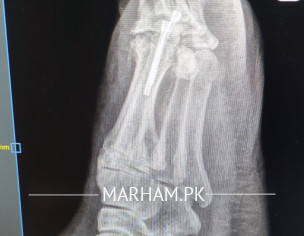

AoA, kindly ye meri mother ki xray report daikh kar bta dain k operation theek ho gya hai, X-ray main fracture nazar aa rha hai lekin, technician ny b kaha k fracture show ho rha hai kisi doctor ko dikha dain. shukria

Need following informations

1- Date of injury or weeks

2- XRay before Surgery

3- XRay just after surgery

4- XRay latest , you already shared

Regards

Osteotomy means cutting the bone to straighten it, usually to relieve pain or improve joint function. After the cut, the bone is held in place with plates, screws or pins while it heals. Most people need a period of limited weight‑bearing followed by physical therapy to rebuild strength and range of motion. Recovery can take several months, and the goal is to return to normal activities, but some patients may still need braces or activity adjustments. The procedure is common for knee, hip or foot problems, and outcomes are generally good when the surgeon’s plan matches the patient’s anatomy and the rehab is followed closely. If you’re considering it, talk to an orthopedic surgeon about your specific condition, the expected healing time, and any lifestyle changes that will help you recover fully.